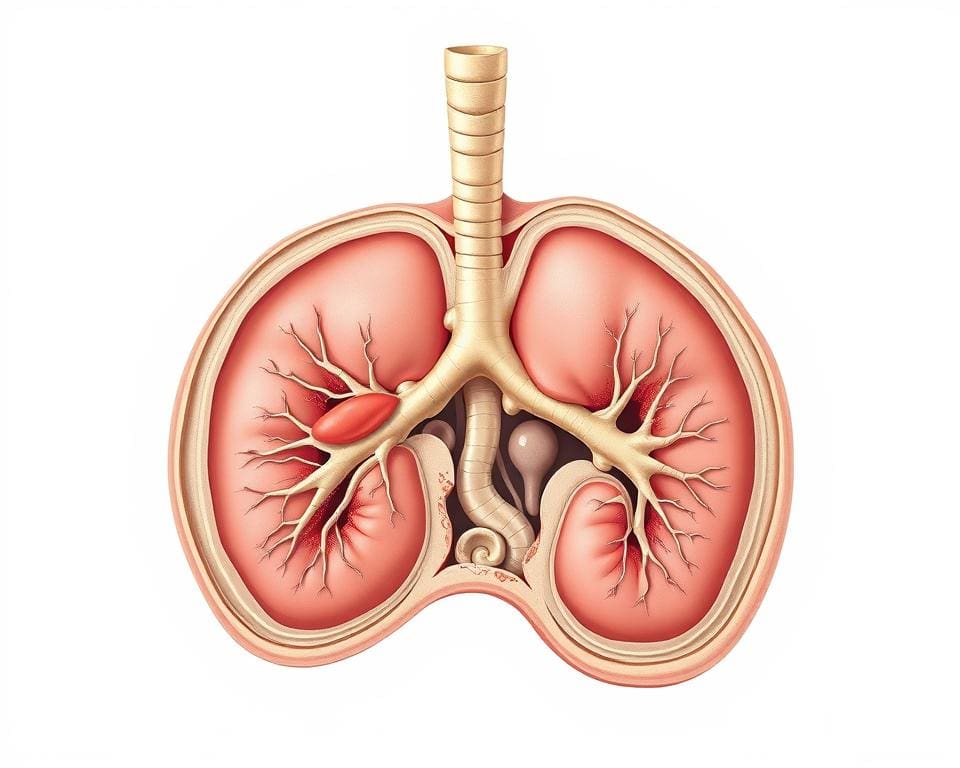

Das Immunsystem besteht aus verschiedenen wichtigen Organen, die eine entscheidende Rolle in der Immunfunktion spielen. Jedes dieser Organe trägt zur Gesamtgesundheit bei, indem es zusammenarbeitet und die Abwehrmechanismen des Körpers unterstützt. Ihre Zusammenarbeit ist für eine effektive Immunantwort unerlässlich.

Die wichtigsten Organe des Immunsystems

Zu den zentralen Immunsystem Organen zählen:

- Milz

- Thymusdrüse

- Lymphknoten

- Knochenmark

Die Milz ist verantwortlich für das Filtern von Blut und das Entfernen alter oder geschädigter Blutzellen, während die Thymusdrüse T-Zellen reift und trainiert. Lymphknoten bilden Filterstationen für Immunzellen und sind wichtig für die Abwehr von Pathogenen.

Wie diese Organe zusammenarbeiten

Die Zusammenarbeit der Immunorgane ist komplex. Sie kommunizieren ständig und koordinieren ihre Aktivitäten, um eine schnelle und effektive Reaktion auf Infektionen zu gewährleisten. Zum Beispiel kommen Immunzellen, die in der Milz und den Lymphknoten produziert werden, in Kontakt mit möglichen Eindringlingen. Durch diese systematische Zusammenarbeit können die Organe effizient auf Bedrohungen reagieren und die Immunfunktion optimieren.

Die lymphatischen Organe

Die lymphatischen Organe spielen eine entscheidende Rolle im Immunsystem des Menschen. Sie unterstützen die Abwehr von Krankheiten und Infektionen, indem sie Immunzellen produzieren und aktiv an der Immunantwort teilnehmen. Zu diesen Organen gehören unter anderem die Lymphknoten und die Milz, die jeweils einzigartige Funktionen innerhalb des lymphatischen Systems übernehmen.